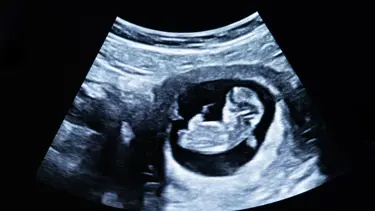

Hindistan’da son derece nadir görülen tıbbi bir vaka yaşandı. 32 yaşında anne olmaya hazırlanan bir kadının rutin taramaları sırasında doğmamış bebeğinin karnında kemik içeren bir yapı tespit edildi. Yapılan ileri tetkikler sonucunda, bebeğin içinde iki farklı fetüs daha bulunduğu ortaya çıktı.

Kadın, 1 Şubat’ta sağlıklı bir erkek bebek dünyaya getirirken, doktorlar gelişimini tamamlayamayan iki fetüsü bebeğin karnından başarıyla çıkardı.

Taramayı gerçekleştiren Dr. Prasad Agarwal, “Karnında fetüs benzeri bir yapı bulunan, normal büyüyen bir bebek gördüm. Bu, dünyanın en nadir vakalarından biri” dedi.

Anne ve bebeğin sağlık durumunun iyi olduğu belirtilirken, içeride gelişen diğer iki fetüsün hayatta kalamayacak kadar az gelişmiş olduğu bildirildi.